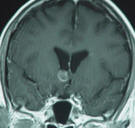

MRI of the brain was done

07-December-2009 and MRA of the brain with MRI

of the brain with contrast repeated

08-December-2009 showing the subependymar mass

in the region between the head of the right

caudate nucleus and the anterior commissure.

There was no aneurysm and there was still

enhancement of the ring around the mass, which

slightly shrunken in comparison to the MRI

performed 17-Novemeber-2009. |